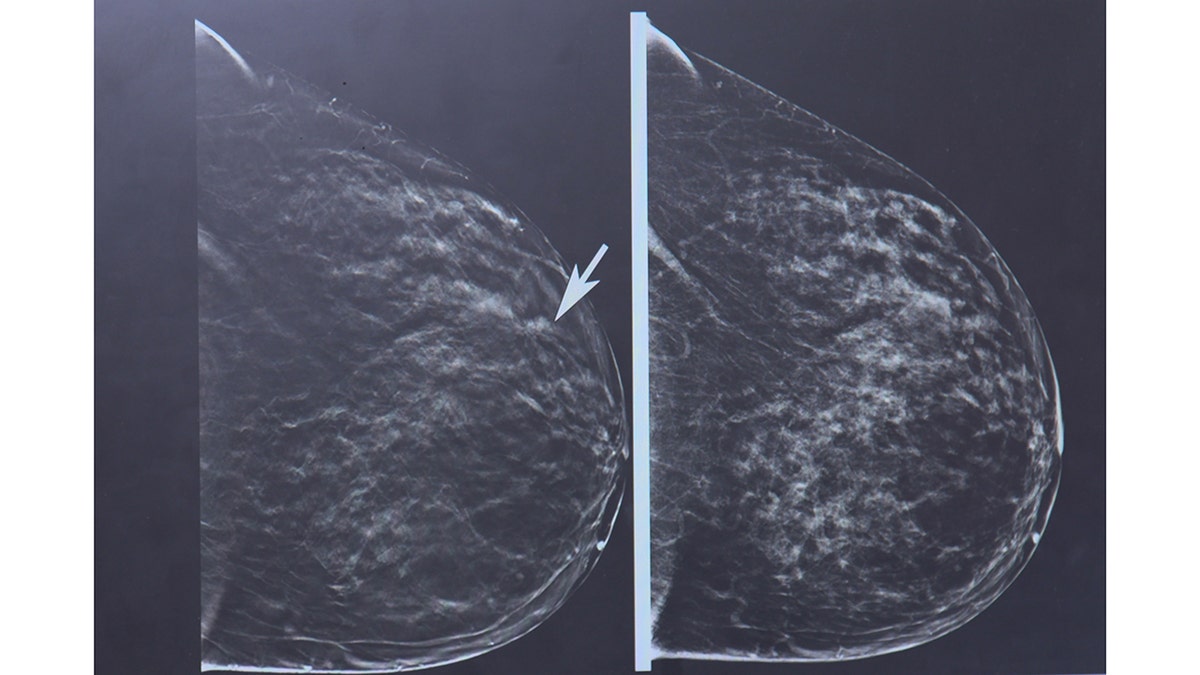

Así es como el cáncer de mama lobbler puede estar presente en la mamografía. MD, Arya Roy menciona la nube de imágenes, que le pedirá que recomiende una exploración adicional. (Universidad Estatal de Ohio)

En lugar de una abrazadera de células formadoras de tumores, las células cancerosas crecen en una larga disciplina, por lo que aparecen como “espesor fino” en las mamografías. Según la OSU, esto significa que puede ser difícil de identificar hasta que se propague a otras partes del cuerpo.